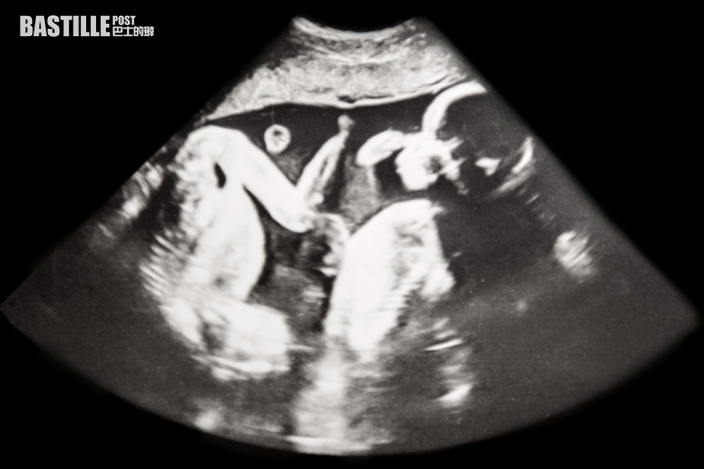

英國一名女子在懷孕三週的時候產檢發現,自己竟在孕期「二次懷孕」,肚中再添一名胎兒,變成雙胞胎。之後她順利生下一對龍鳳胎,罕見例子全球過往記錄僅有十幾例。

據英國《每日郵報》報導,39歲女子羅伯茲(Rebecca Roberts)發現自己懷上「雙胞胎」時十分震驚,她表示「前2次產檢完全沒有第二胎的跡象,我都不知道懷孕的時候還有可能再次受孕」,而照了超聲波之後,醫生指她懷了一對龍鳳胎,較早受孕的是男孩,二次受孕的是女孩。